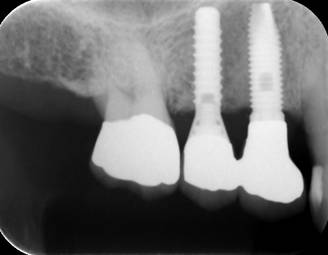

ストローマンインプラントとスプラインインプラントが隣り合わせに埋入されています.このころストローマンからスプラインに変えています。変えた理由は前歯部の審美性に優れていること、アバットメントの自由度があること、抜歯後すぐに埋入できるなどでした。